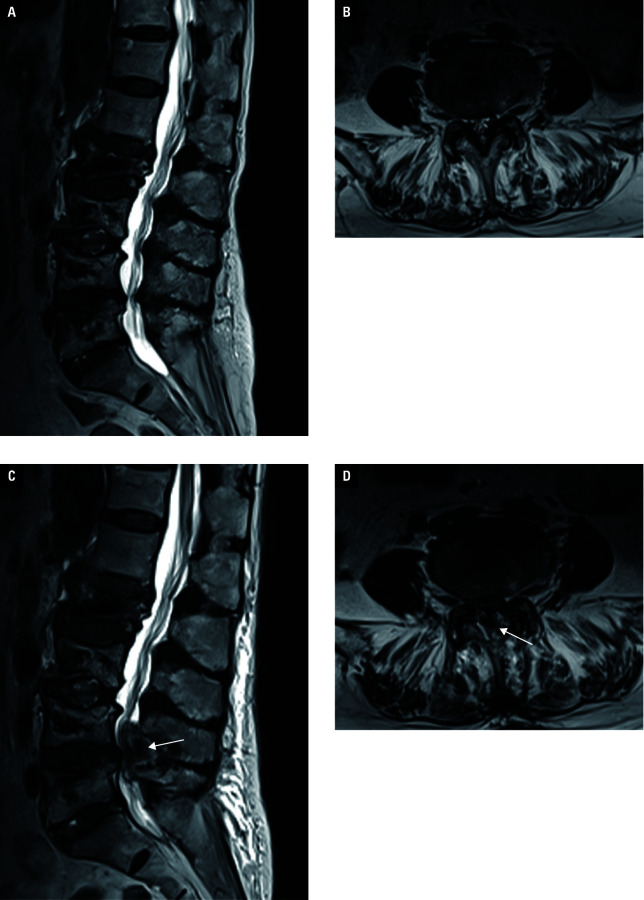

Abstract Image